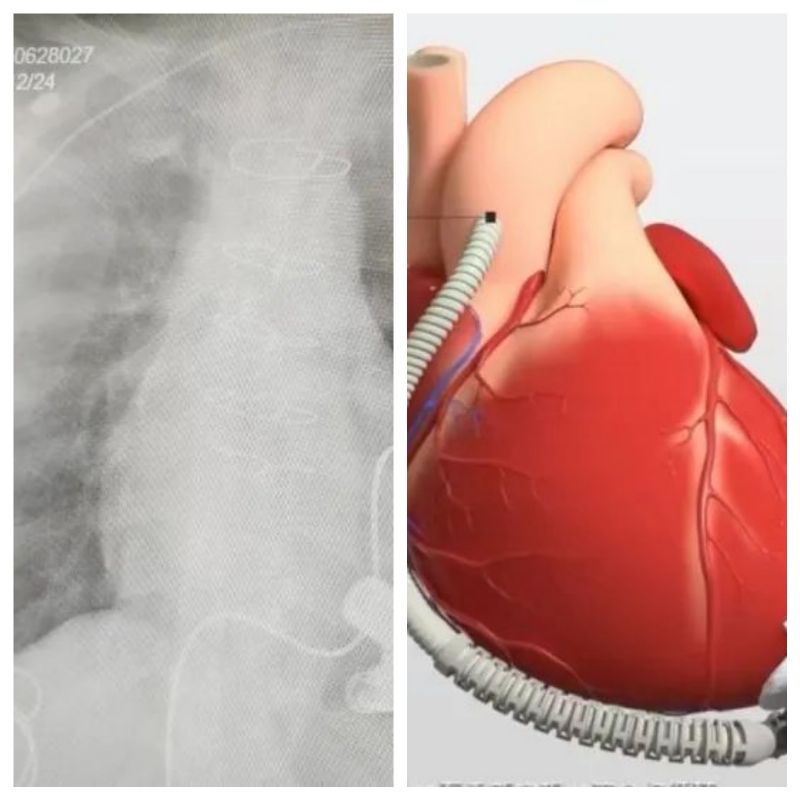

術(shù)前心臟超聲評(píng)估 術(shù)后心臟超聲

“既要確保人工心臟的穩(wěn)定性,又要平衡機(jī)械心與自體心臟的血流關(guān)系,抗凝方案的調(diào)整更是容不得半點(diǎn)誤差”。武小剛介紹:術(shù)中,通過(guò)食道超聲精準(zhǔn)定位泵頭嵌入心尖的方向,人工血管精準(zhǔn)吻合于升主動(dòng)脈。歷經(jīng)2小時(shí)精細(xì)操作,人工心臟順利啟動(dòng),規(guī)律的"機(jī)械心跳"聲在監(jiān)護(hù)儀上響起這顆"生命引擎"開(kāi)始以每分鐘3~5升的血流量,為李某某(化名)全身輸送足量的血液及氧氣。